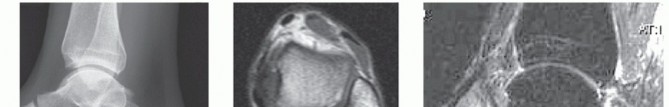

DEFINITION Medium-sized osteochondral defects of the talar dome May approach the talar shoulder (transition o…